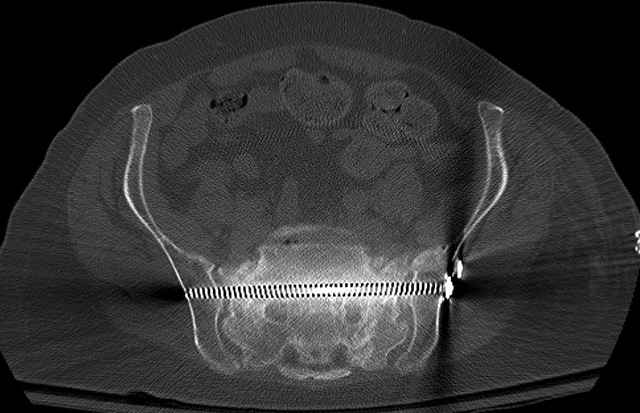

Pelvic CT Scan - 3 Months After Fall

Ramus Fractures